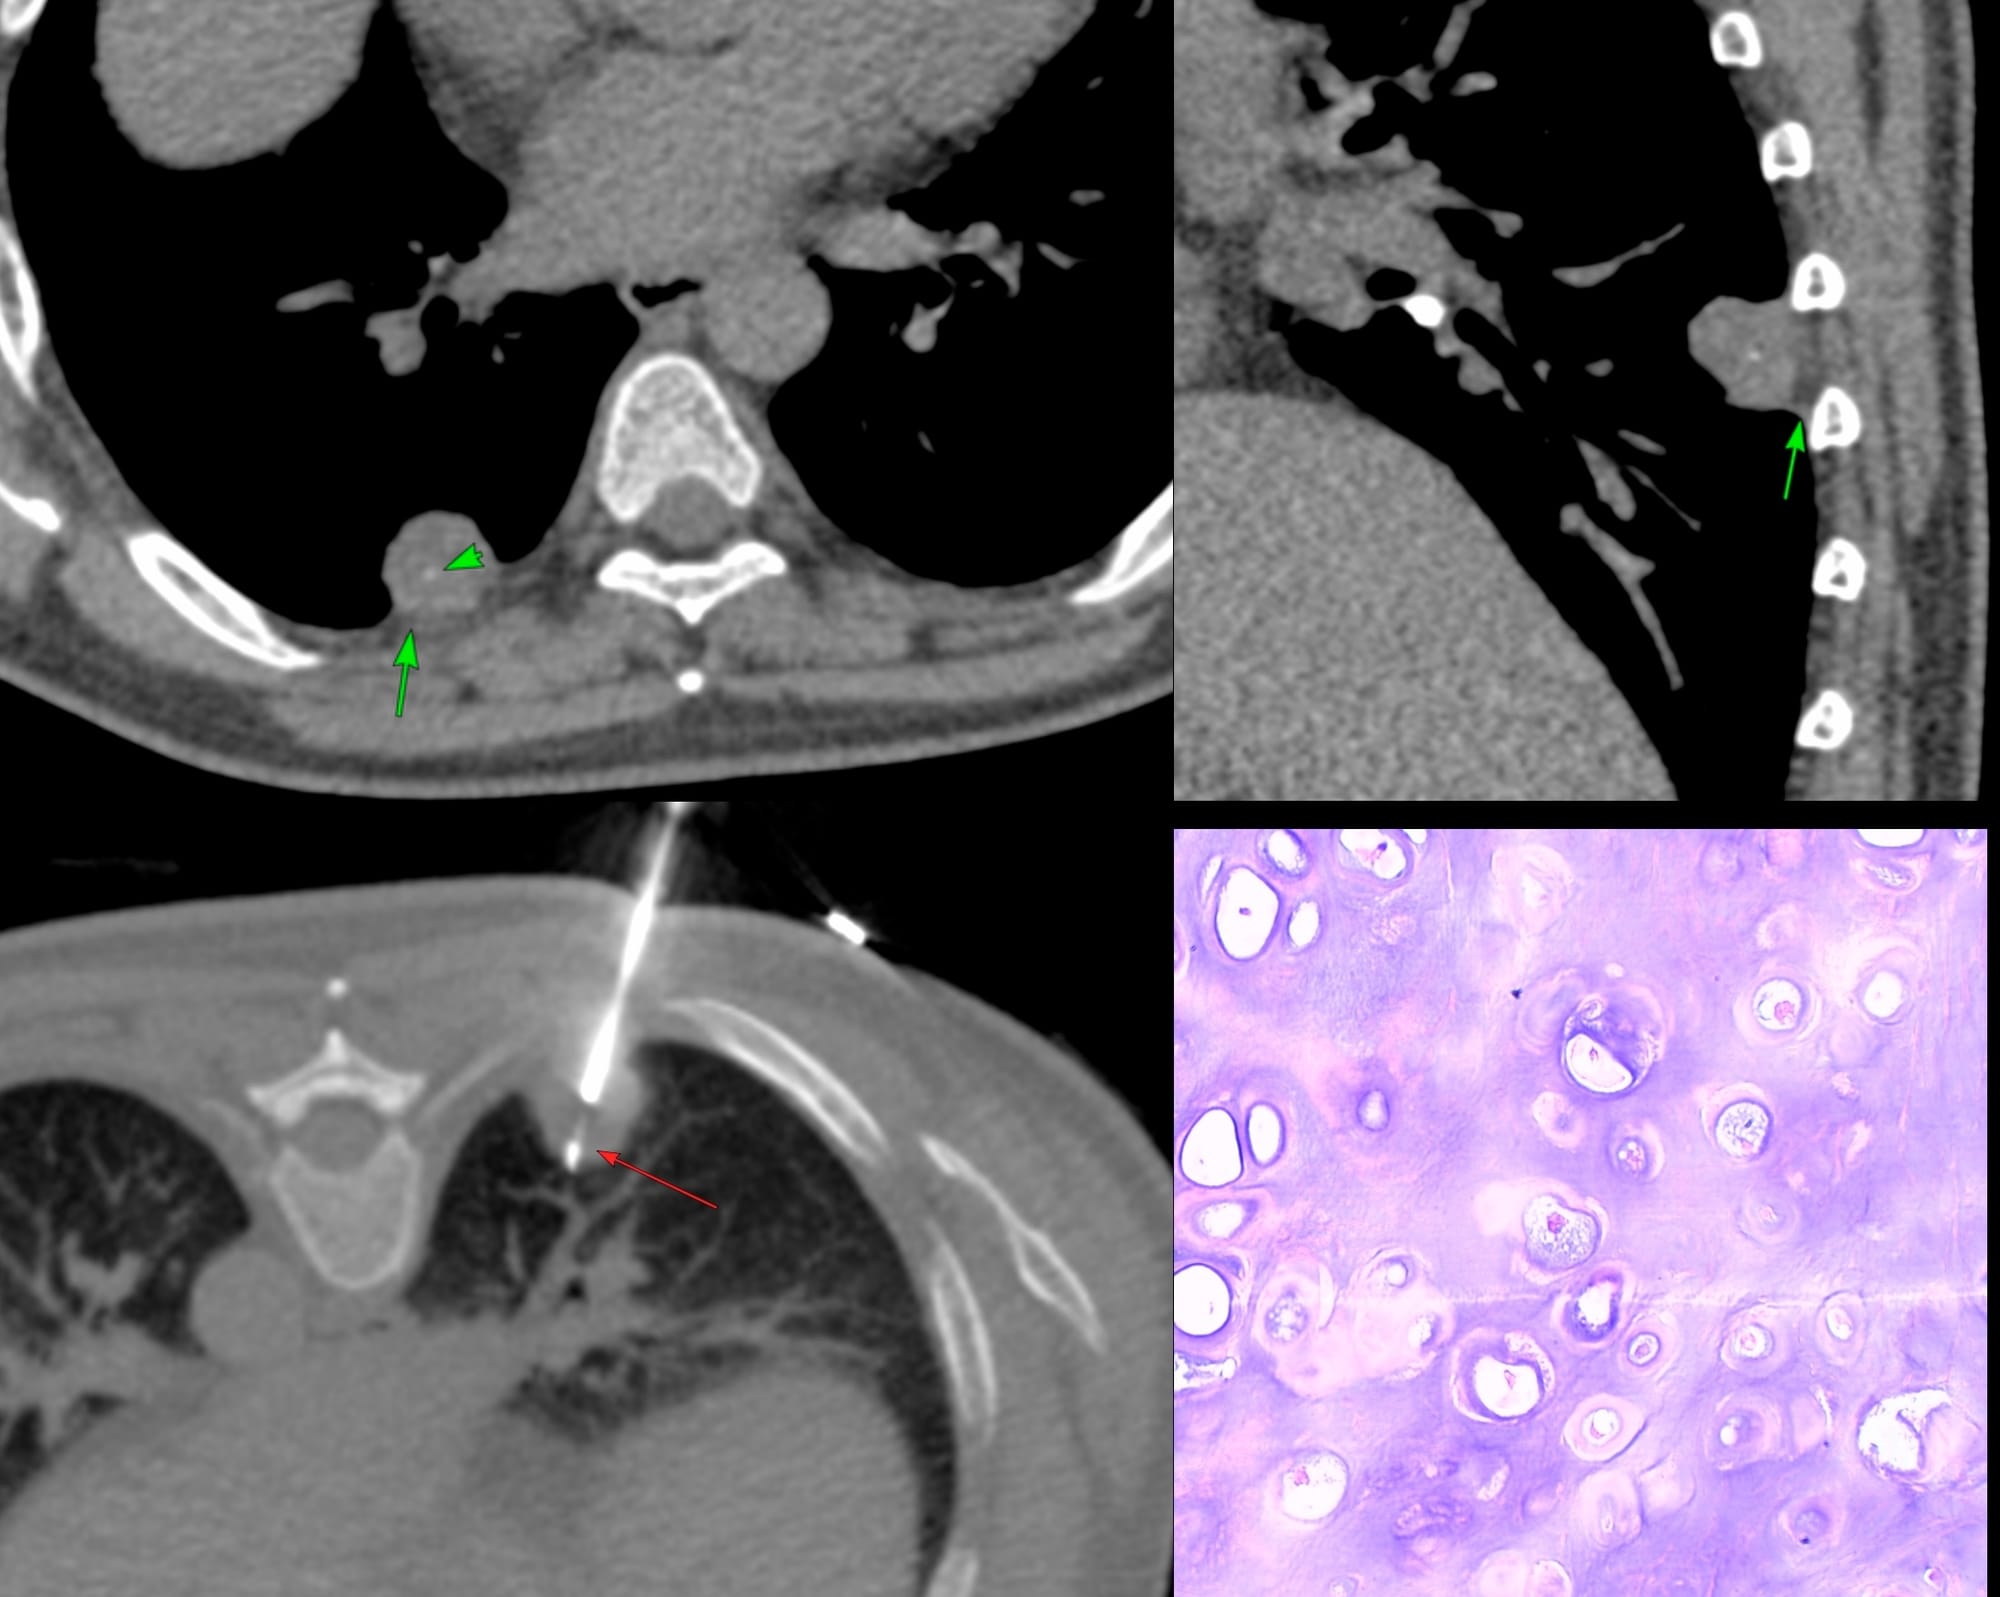

56-years old with an incidentally detected lung nodule in the superior segment of the right lower lobe of the lung. It showed one calcific speck. No contrast. No PET. There was extrapleural fat retraction, suggesting this could be extra-pulmonary.

On biopsy, it was firm. Histopath shows cartilage.

This is a peripheral chondroid hamartoma of the lung. Likely so longstanding, that the pleura has puckered around it.